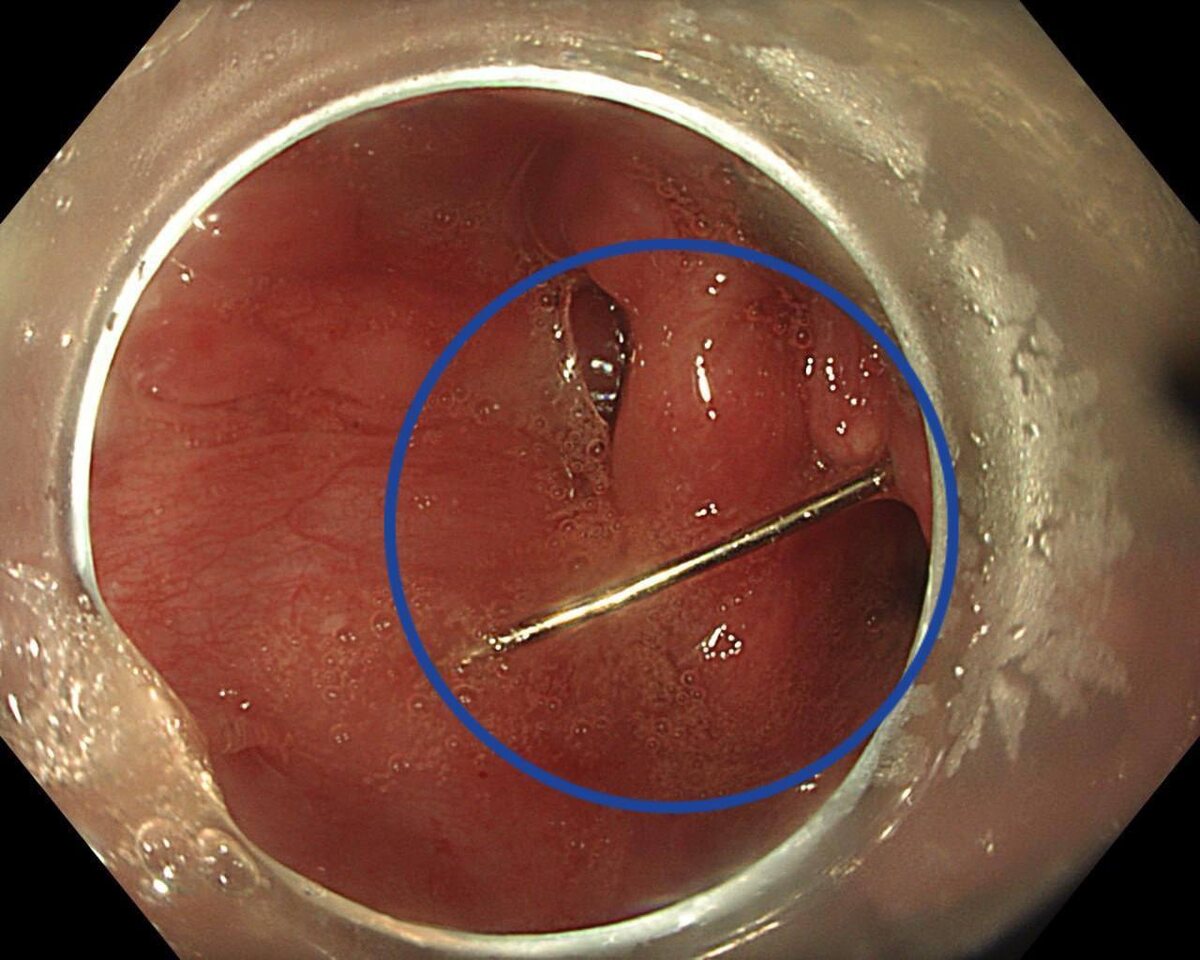

🪡 В Подмосковье девочка-подросток проглотила иглу из любопытства. 15-летняя девочка из любопытства случайно проглотила иголку, родители немедленно обратились за медицинской помощью. Пациентку доставили в Детский научно-клинический центр им. Л.М. Рошаля с жалобами на сильную боль в горле, рвоту с кровью и затрудненное глотание. Врачи при обследовании обнаружили инородное тело: «Операция прошла успешно и без единого разреза», — сказал заведующий отделением эндоскопических методов диагностики и лечения Александр Иноземцев. Москва. Новости 24/7

15-летняя девочка из любопытства случайно проглотила иголку, родители немедленно обратились за медицинской помощью. Пациентку доставили в Детский научно-клинический центр им. Л.М. Рошаля с жалобами на сильную боль в горле, рвоту с кровью и затрудненное глотание. Врачи при обследовании обнаружили инородное тело:

«Операция прошла успешно и без единого разреза», — сказал заведующий отделением эндоскопических методов диагностики и лечения Александр Иноземцев.